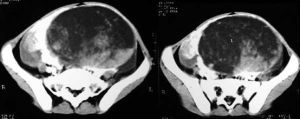

內胚竇瘤卵巢內胚竇瘤又稱卵黃囊瘤是卵巢惡性生殖細胞瘤(OGCT)中最常見的類型之一。多發生在年輕婦女和青少年,發病中位年齡為19歲。由於卵巢內胚竇瘤生長快,容易...

流行病學 病因 發病機制 臨床表現 併發症卵黃囊瘤(yolk sac tumor)是卵巢惡性生殖細胞瘤(OGCT)中最常見的一種腫瘤。世界衛生組織(WHO)在卵巢腫瘤分類中將原通用名卵巢內胚竇瘤...